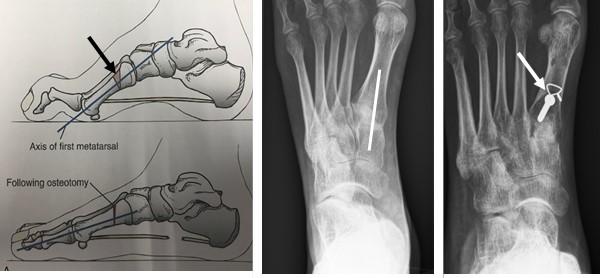

Bij een calcaneus osteotomie wordt het hielbot doorgezaagd en meer naar de buitenzijde verplaatst. De achtervoet komt zo meer van de “O” positie in een “X” positie.

Het vastzetten van beide botdelen gebeurt meestal met een schroef vanuit de hiel, middels een apart litteken.

Figuur 1: Voorbeeld van een calcaneus osteotomie. H=hielbot (calcaneus). De witte streep op het linker plaatje is de locatie van het litteken. De Rode pijl wijst naar de schroef. Op het meest rechtse plaatje zie je de verschuiving van het hielbot naar de buitenzijde